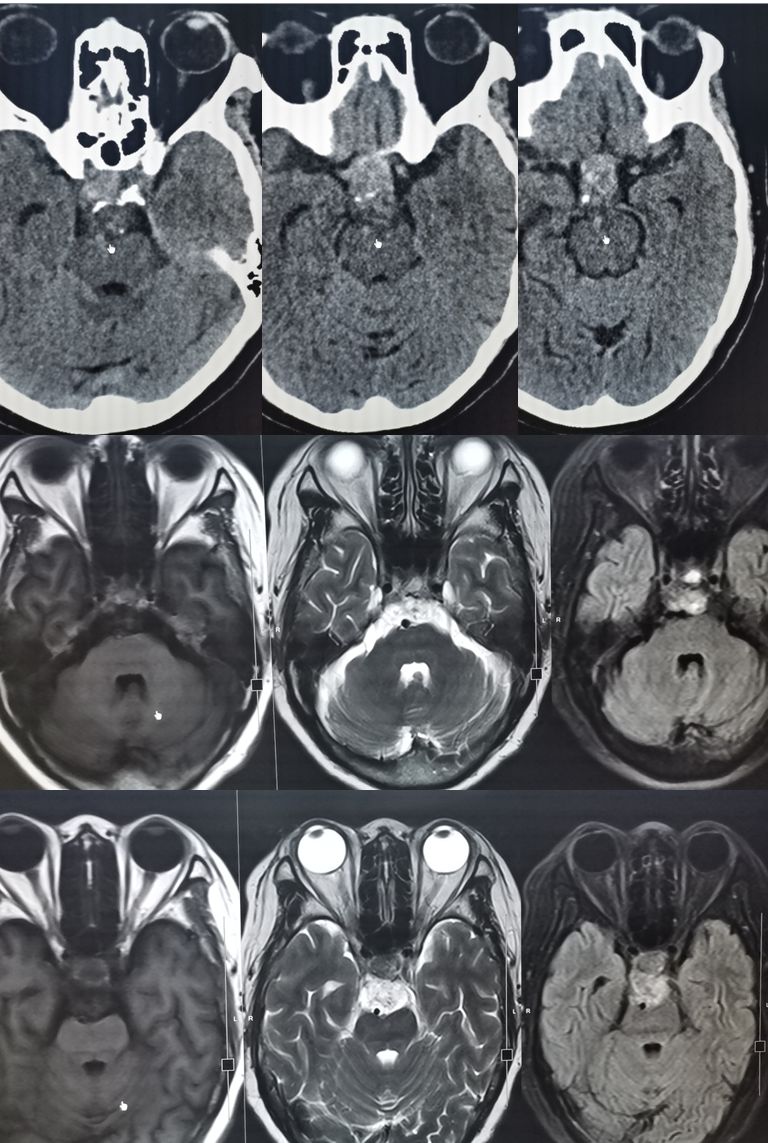

66岁女性,头痛原因待查。

答案:颅底脊索瘤(chordoma)。脊索瘤是一种罕见的缓慢生长的恶性骨肿瘤,通常发生在脊柱或颅底。来源于残存的脊索组织,具有肉瘤的部分特点。通常在40-70岁发病。男性多于女性。脊索瘤可以发生在脊柱和颅底的任何部位。CT一般表现为溶骨性骨质破坏,常伴有膨胀性软组织肿块,内有散在斑片状钙化,少数边缘表现为骨质硬化。MRI信号呈长T1、长T2信号,信号不均匀,增强后多呈中度至明显不均匀“蜂窝”状强化。矢状位桥脑腹侧呈“指压状”凹陷。要和垂体瘤、脑膜瘤相鉴别。治疗包括外科手术、放疗和靶向治疗等。